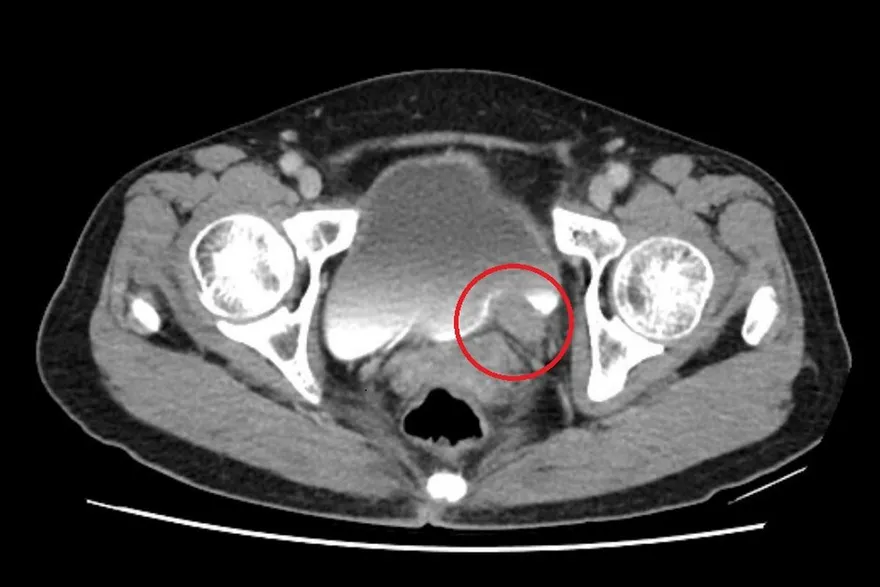

5公分「輸尿管腫瘤」險致腎衰竭!醫:無痛血尿勿輕忽

間歇性無痛血尿

輸尿管

輸尿管腫瘤

腎水腫

泌尿上皮癌